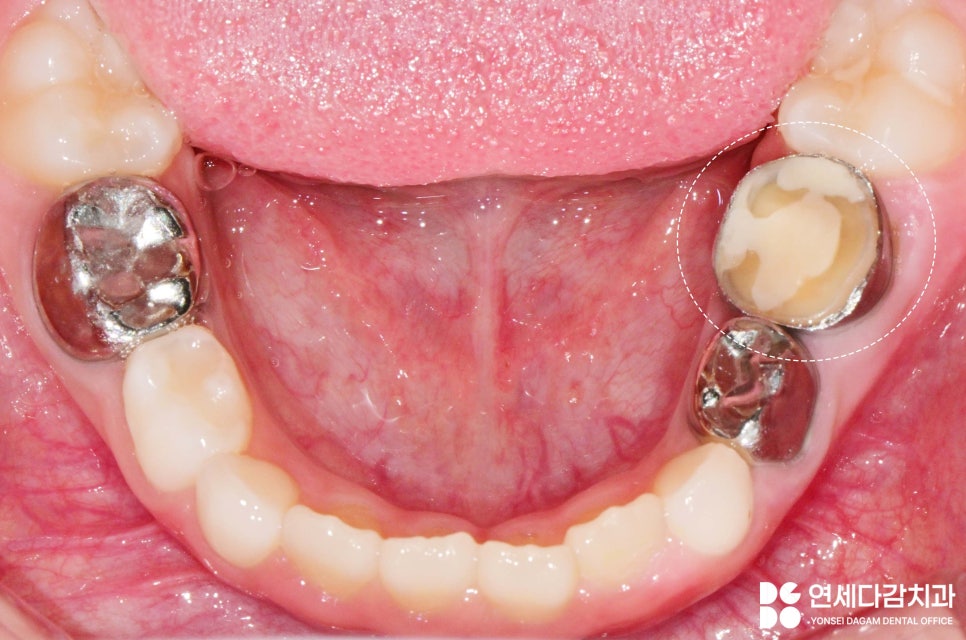

그러나 이것이 부러져서

교체를 할 때는 치아가 무너지면서

빠질 수 있습니다.

광범위한 부분이 충전재로 수복되어 있고

기존 치아 구조가 얇은 상태에서

힘을 가하면 부서질 수 있습니다.

25.07.17

그러나 아직 영구치로 교체될

시기가 꽤 남았기도 했고,

고름이 나오고

통증이 지속되는 상황이라

치료가 필요합니다.

이대로 방치하면 부러진 크라운 틈으로

세균이 들어와 감염을 일으키고,

이는 더 심각한

문제로 발전할 수 있습니다.